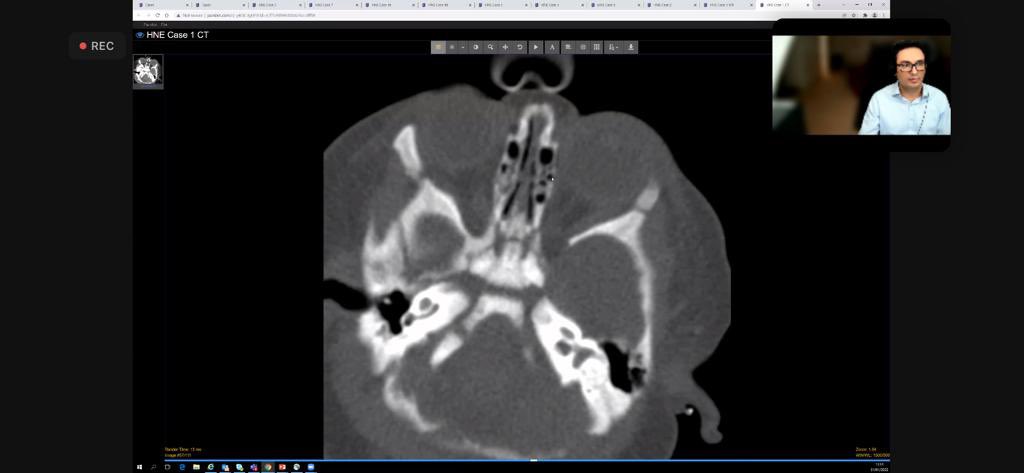

Wow! INCREDIBLE case-rich session from my amazing colleague @DrAtaSiddiqui top tips, practical pearls, exemplary live cases with audience participation using @pacsbin &interactive polls. Stellar job! 👏🏾👏🏾 @theBSNR @BSNRTrainees @BSHNI_UK @@ESNRad @ESHNRSociety @ASHNRSociety